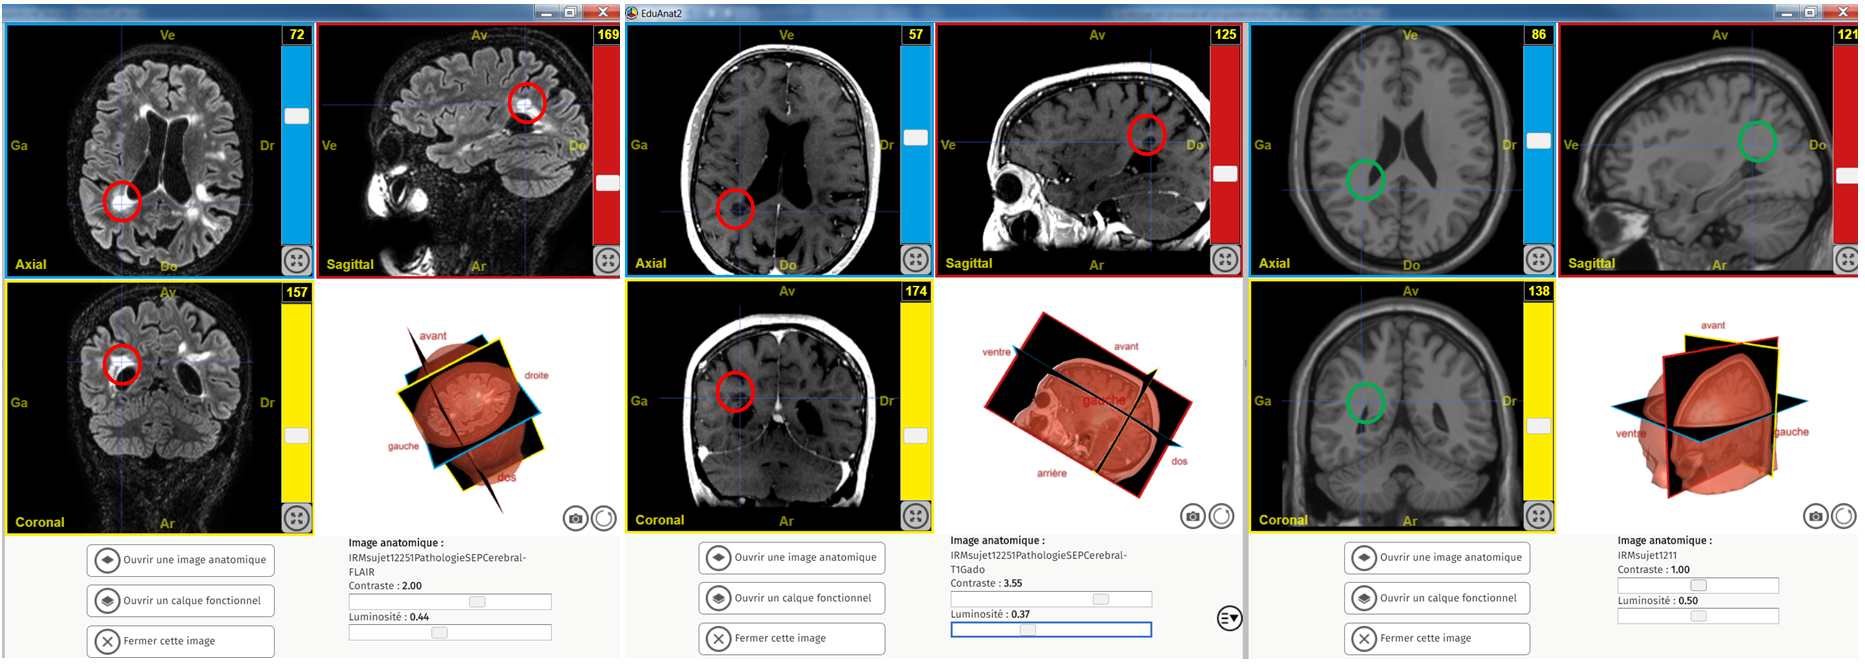

SEP 3 images